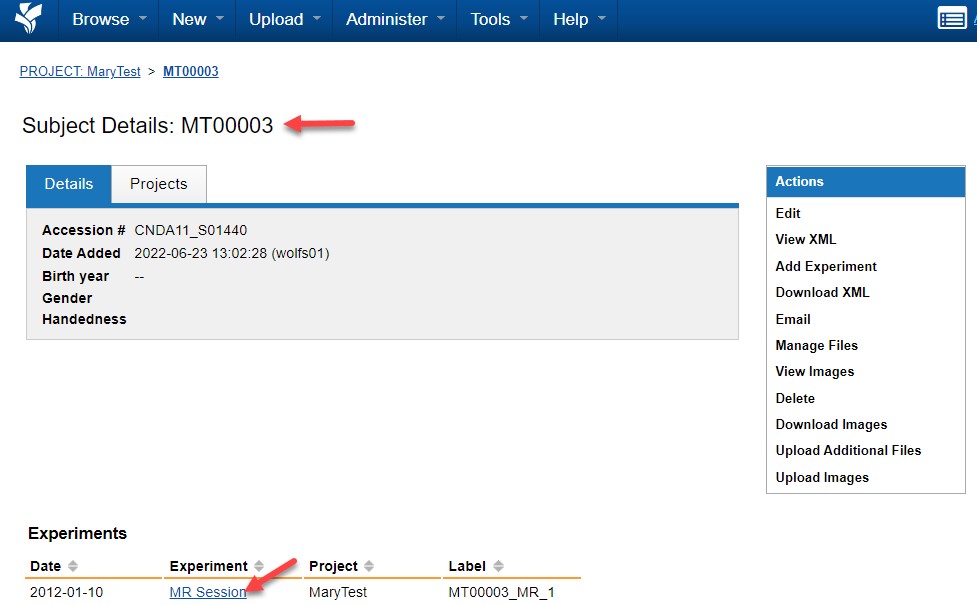

Verifying Upload in CNDA

After upload completes:

- Log in to CNDA.

- Navigate to your project.

- Select the subject.

- Open the session.